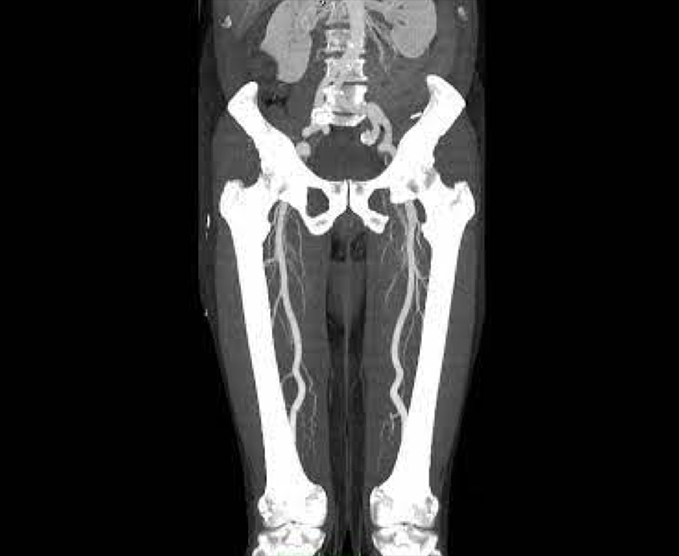

Angiotomografías

La angiografía por TC (ATC) combina una tomografía computarizada con la inyección de una tintura de contraste. TC significa tomografía computarizada. Esta técnica es capaz de crear imágenes de los vasos sanguíneos para detección de anomalías.

- Angiografía de MPS